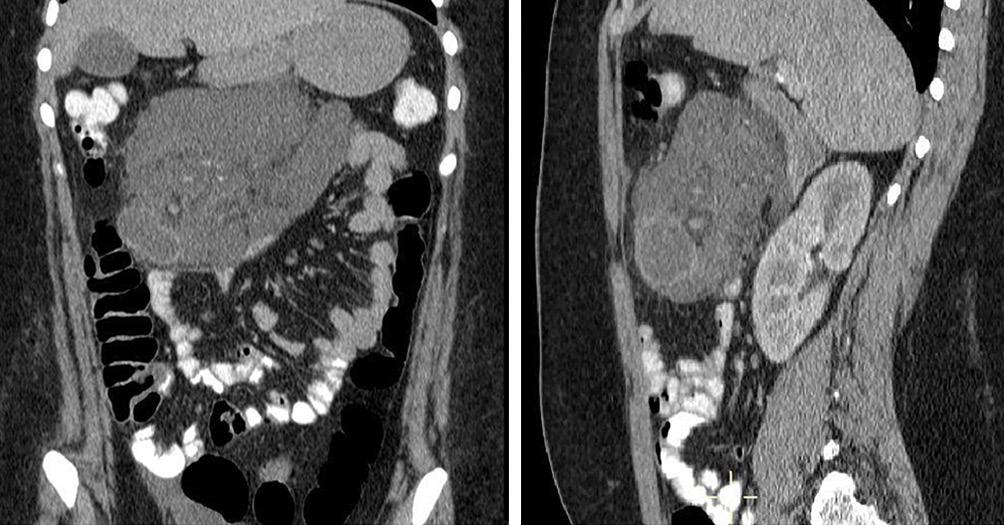

La endoscopía superior es un procedimiento fundamental para el diagnóstico, la evaluación de la respuesta al tratamiento y el monitoreo a largo plazo de la actividad de la EEo. Los hallazgos endoscópicos típicos incluyen edema (reducción de vascularidad), anillos esofágicos fijos, exudados blancos, surcos longitudinales, estenosis, estrechamiento de la luz esofágica, friabilidad de la mucosa (mucosa en papel crepé) y una consistencia firme de la mucosa al realizar biopsias (signo de “tracción" o "resistencia”) en pacientes con fibrosis (Figura 1). Estos hallazgos no son patognomónicos y no constituyen un criterio diagnóstico; sin embargo, cuando se evalúa de forma cuidadosa, en la gran mayoría de los casos se pueden observar.19-21

En el panel A se observa un esófago con edema difuso y pliegues longitudinales; en el panel B se aprecia edema con pliegues y exudados blanquecinos; en el panel C se evidencia un estrechamiento luminal acompañado de anillos esofágicos y exudados; y en el panel D se muestra un desgarro mucoso posterior a la dilatación con bujía de Savary, hallazgo esperado tras este procedimiento terapéutico.

Figura 1. Características endoscópicas de la esofagitis eosinofílica